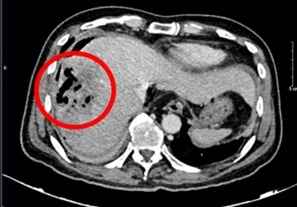

Hình ảnh chụp cắt lớp vi tính ổ bụng của bệnh nhân. Ảnh: BVCC. |

Đáng chú ý, chỉ số AFP giảm mạnh theo thời gian, từ 648,1 ng/ml vào thời điểm bắt đầu điều trị xuống còn 9,2 ng/ml sau 20 chu kỳ, tiệm cận ngưỡng bình thường. Các kết quả chụp cắt lớp vi tính cũng ghi nhận khối u gan thu nhỏ rõ rệt, không còn tăng sinh mạch hay huyết khối. Kích thước u giảm từ 81 x 51 mm xuống còn khoảng 22 x 45 mm. Theo tiêu chuẩn RECIST 1.1, bệnh nhân đạt đáp ứng một phần.

Theo các bác sĩ, đây là trường hợp ung thư gan giai đoạn trung gian đã điều trị TACE nhiều lần nhưng vẫn đáp ứng rất tốt với phác đồ miễn dịch - kháng tạo mạch. Kết quả này không chỉ giúp kiểm soát bệnh hiệu quả mà còn mở ra khả năng đưa người bệnh từ nhóm không còn chỉ định phẫu thuật trở lại diện có thể cân nhắc can thiệp trong tương lai.